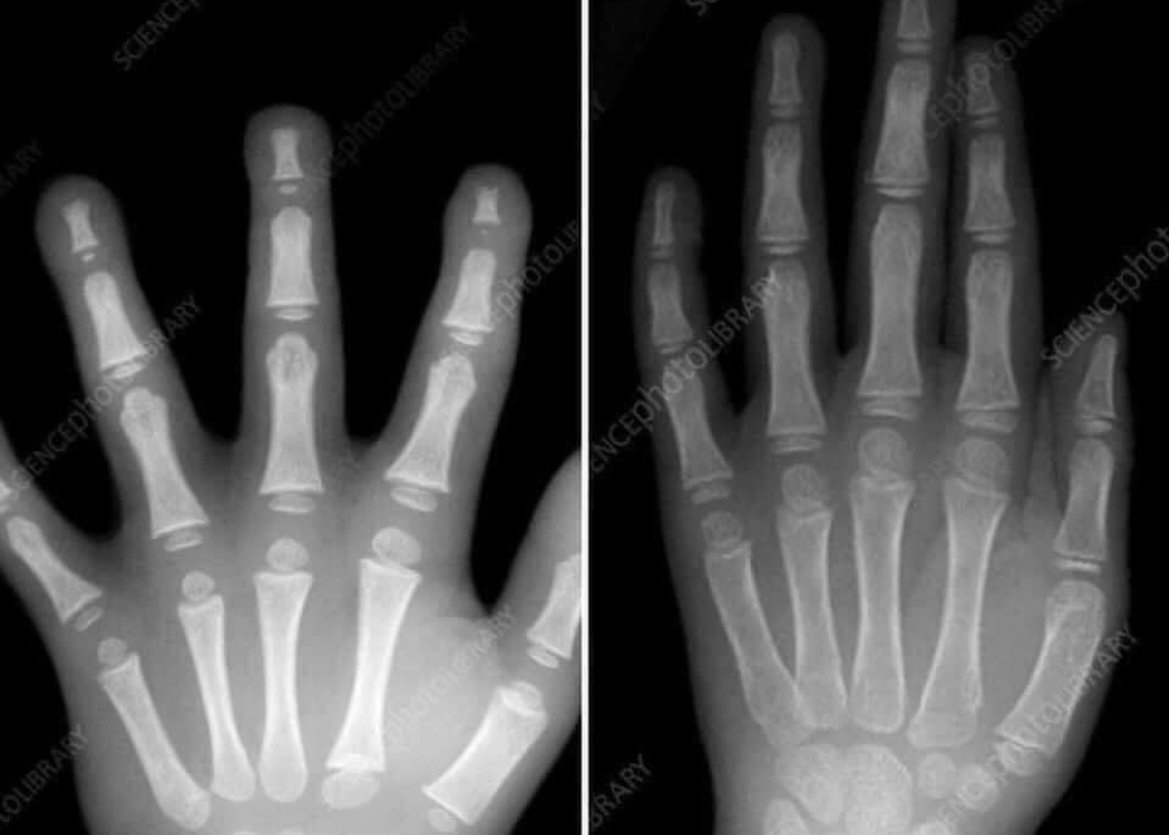

Po sieci krąży zdjęcie, które doskonale oddaje przyczynę, dla której dziecko w wieku przedszkolnym nie tylko nie musi pisać, ale nawet nie powinno. Jego budowa anatomiczna nie jest jeszcze ku temu odpowiednio wykształcona!Środowiska związane z edukacją i rozwojem najmłodszym dzielą się zdjęciem oraz wpisem:

Oto różnica między rączką typowego dziecka w wieku przedszkolnym (po lewej) a rączką typowego siedmiolatka (po prawej). Zastanawiasz się dlaczego dziecko w wieku przedszkolnym nie potrafi jeszcze pisać? Ich dłonie wciąż się rozwijają i nie są w pełni uformowane. Zatem co powinny robić dzieci w wieku przedszkolnym, aby rozwijać rączkę? BAWIĆ SIĘ!

Lepić z Playdough, kolorować, wycinać, kleić, spędzać czas na dworze, bawić się w błocie, robić eksperyment naukowe, układać puzzle itp. Wszystkie te rzeczy pomagają ich dłoniom rozwijać się. Kiedy będą fizycznie gotowe do pisania, zrobią to! Nie musicie ich pospieszać. Dajcie im czas.